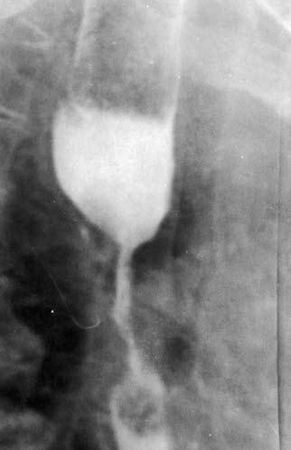

Рис. 42. Рентгенограмма супрастенотического расширения.

На рентгенограмме выше места сужения определяется компенсаторное расширение просвета пищевода, заполненное контрастным веществом

При циркулярном распространении опухоли пищевод на этом участке становится суженным, образуя "раковый канал". Над сужением, как правило, определяется супрастенотическое расширение (рис. 42).